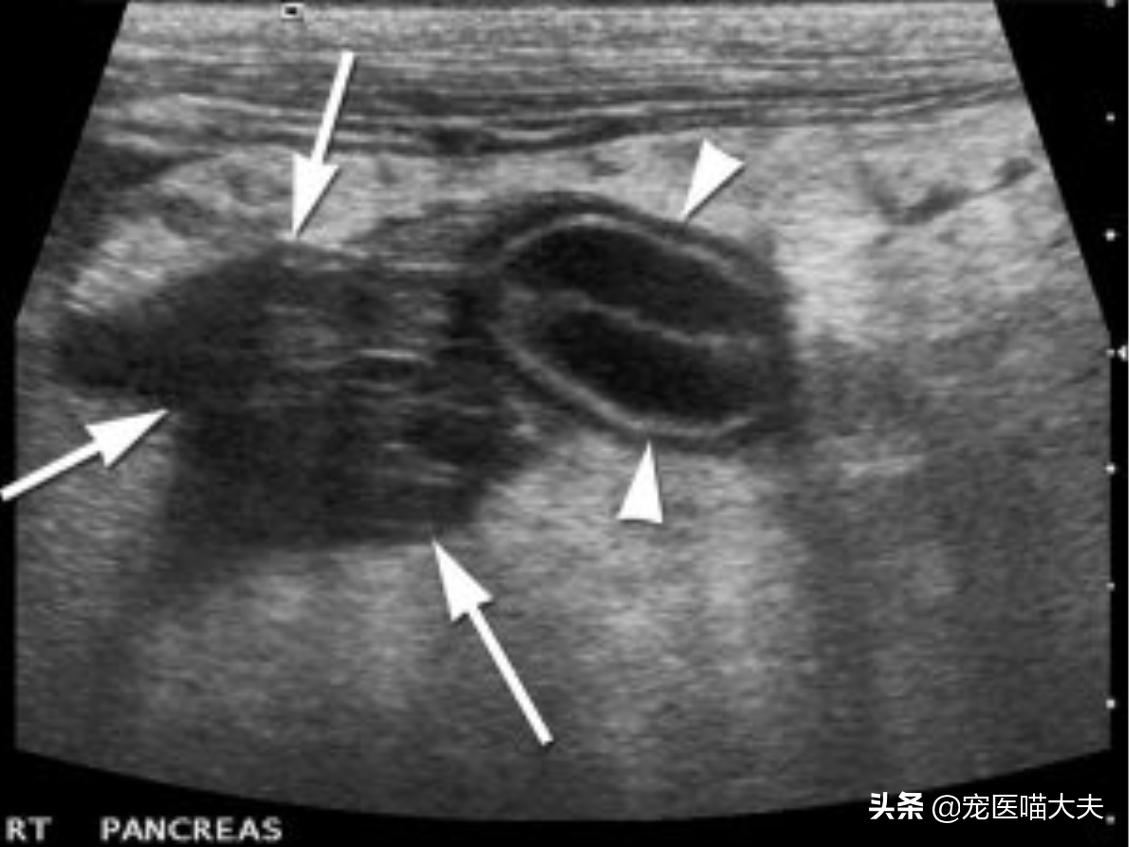

- 超声检查:超声检查结果包括扩大的低回声胰腺、脓肿或假性脓肿等空洞性病变,以及胰管扩张、十二指肠肿胀、胆管扩张和腹膜液等。

超声检查